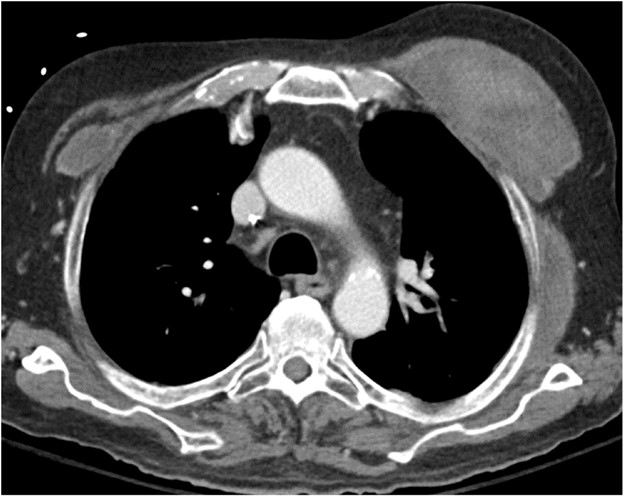

AMR, the less common of the two types of acute rejection, occurs when recipient B lymphocytes create donor-specific antibodies (DSA), donor-specific antigens and DSA form complexes, and the complexes trigger the immune system’s complement pathway. Like patients with ACR, patients with AMR can be asymptomatic; can have nonspecific symptoms such as dyspnea and cough; and can have normal chest imaging or nonspecific imaging findings resembling pulmonary edema such as consolidation, ground-glass opacities, and septal-line thickening. Transplant physicians diagnose patients with clinical versus subclinical AMR and definite versus probable versus possible AMR on the basis of the presence or absence of allograft dysfunction, histology results suggestive of AMR (such as neutrophil arteritis and capillaritis), immunostaining results (positive C4d staining of the capillary endothelium), and the presence or absence of DSA in peripheral blood [4]. Treatments include plasmapheresis and IV immunoglobulin to remove harmful antibodies and to suppress antibody production, respectively. Steroids are not typically used to treat AMR, unlike ACR. Figure 2 shows a patient with AMR.

Fig. 2—Patient with history of bilateral lung transplant who developed antibody-mediated rejection (AMR), which was diagnosed by transbronchial biopsy and donor-specific antibody blood testing. Chest CT at time of AMR diagnosis shows ground-glass opacities and reticulation in both lungs and small pleural effusions.